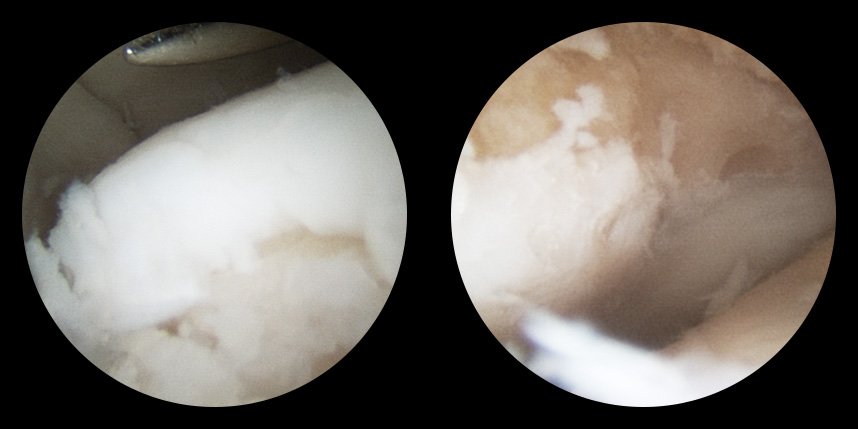

손상된 연골 부위에 작은 구멍을 뚫어 골수에서 나오는 줄기세포를 이용하여 연골 재생을 유도하는 방법으로 근본적으로 섬유연골(정상연골보다는 약한 연골)로 재생된다고 알려져 있습니다.

특수하게 농축하여 제작된 6% 콜라겐(리젠실603) 또는 9% 콜라겐(이엔카티)을 천공술을 시행한 부위에 덮어 주어 미세천공술 단독보다 좋은 치료 결과를 기대할 수 있습니다.

본원에서는 미세천공술, 콜라겐주입술, 카티스템 치료를 주로 하고 있습니다.

타병원 미세천공술 실패 후 통증으로 내원하신 사례